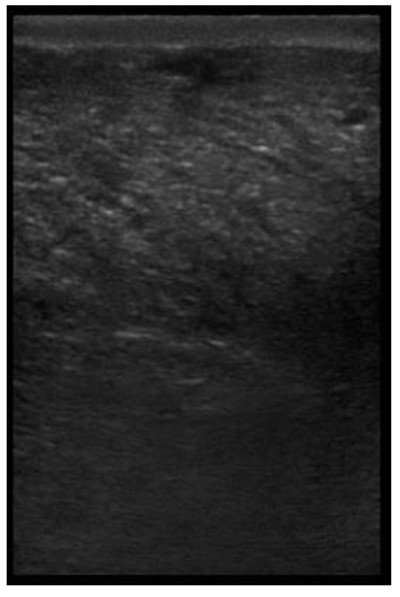

The image processing was undertaken using ImageJ software [28] as used by Abràmoff et al. [29]. The scales between pixels and millimetres were calculated based on the number of pixels, the scanning depth (mm), and the transducer width (mm) (Figure 4). This method relies on the ability of the operator to interpret and identify lines on the images. To standardize the assessment compartment depth, drawing templates were created for each time point as used by Molenaar et al. [30] and included four representative images from four different yearling ewes with and without the lines drawn for each compartment (Appendix A). The total depth of mammary gland conservative (MTc) was the smallest likely demarcation (abdominal wall) of the mammary gland (Figure 5a), and total depth of the mammary gland generous (MTg) was the largest likely demarcation of the mammary gland visible on the image [30] (Figure 5a). The MTc, MTg, fat pad (FP), parenchyma (PAR), and gland cistern (GC) depths were estimated at the deepest point for each sub-compartment, excluding the skin layers, using the straight tracer (Figure 5a) and were expressed in millimetres.

Figure 5.

(a) Demonstration of delimitations of the mammary total depth conservative (MTc) and generous (MTg), mammary gland cistern (GC), parenchyma (PAR) and the fat pad (FP) and (b) Demonstration of randomly positioning of regions of interest (1, 2, 3) in the parenchyma.

Appendix A. Drawing Templates of Mammary Ultrasound Images in Late Pregnancy, Early Lactation and Weaning in Yearling Ewes

Drawing template of mammary ultrasound images at weaning (100 days of lactation; L100) in four different yearling ewes.